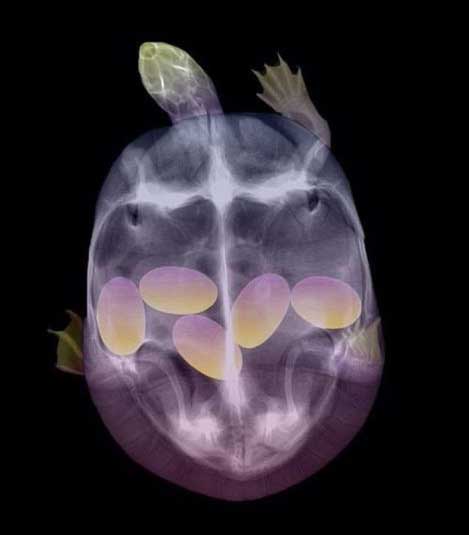

5. カメ